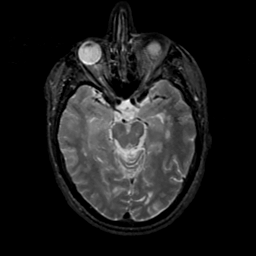

MR Study #17, July 7, 1991 -- Slice #19